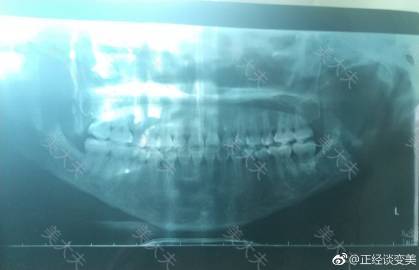

我一直以为下颌是没切多少今天其他医院拍片,医生说:你这个下颌切挺狠啊,几乎沿着神经线 我找彭喆拆钉的时候只是让他随便切切没想到挺负责给我切那么多😂我一直以为随便切切,看起来还挺自然的 看来彭喆做切最多的方法也可以,以前他一直说自己可以这么做,看了ct还是很实在👌 切的多不多,我觉得还真是和自我评价有关,我有个闺蜜做了,做完以后觉得自己脸还不够小,结果拿以前照片一比,靠那个大方脸真是自己? 鼻子七天了比前几天好多了,前几天真是丑爆了,差点精神崩溃,鼻子医生说观察观察,如果觉得再高或者下垂过段时间拿出来修(感谢医生认真负责🙏)其实做鼻子就做好了要几修的准备 接下来eve包眼角提日程,不考虑其他家是因为我喜欢园眼角,我要包得越多越好的